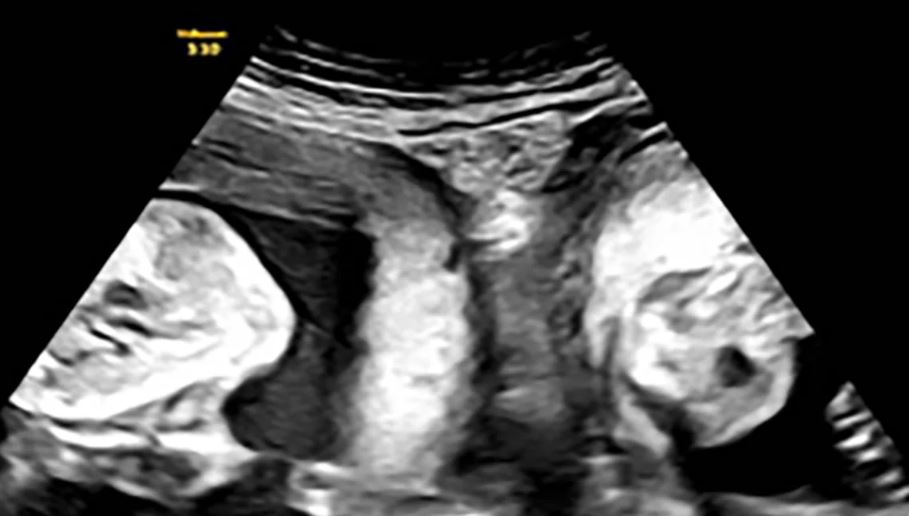

Ali u januaru Li je ponovno zatrudnjela i otkrila je tokom ranog ultrazvuka da ne očekuje samo jedno dijete već blizance – po jednog u svakoj maternici.